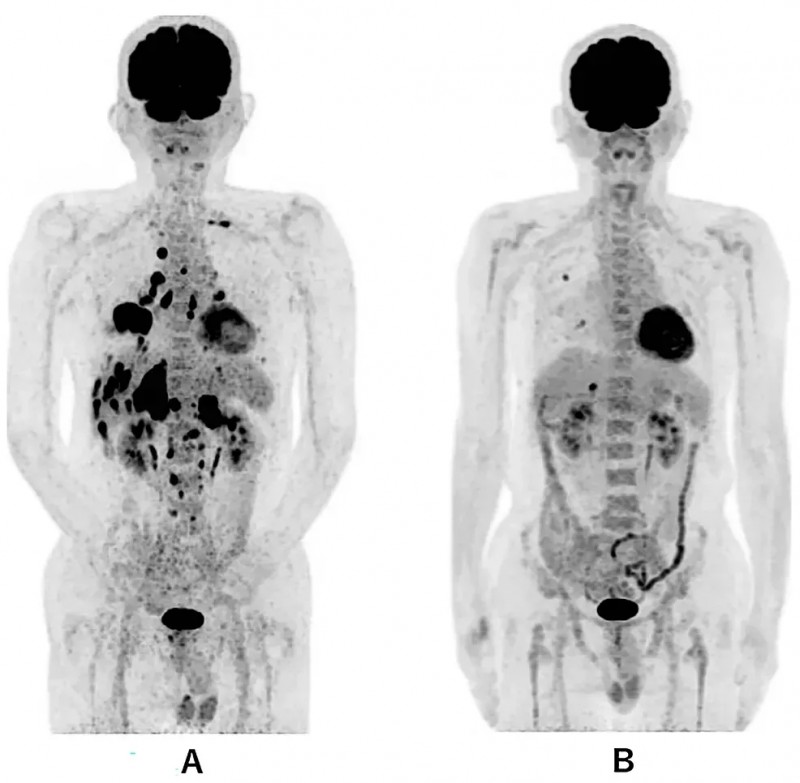

结果显示:患者确诊时全身PET-CT可见右下肺原发肿瘤,及双侧多发肺内转移、多发肝转移、双侧肾上腺转移、多发骨转移。而接受联合治疗第479天的PET-CT显示,仅残留右肺1.0cm转移灶、肝脏1.7cm转移灶,其余部位未见异常(详见下图)。

▲图源“Cureus”,版权归原作者所有,如无意中侵犯了知识产权,请联系我们删除